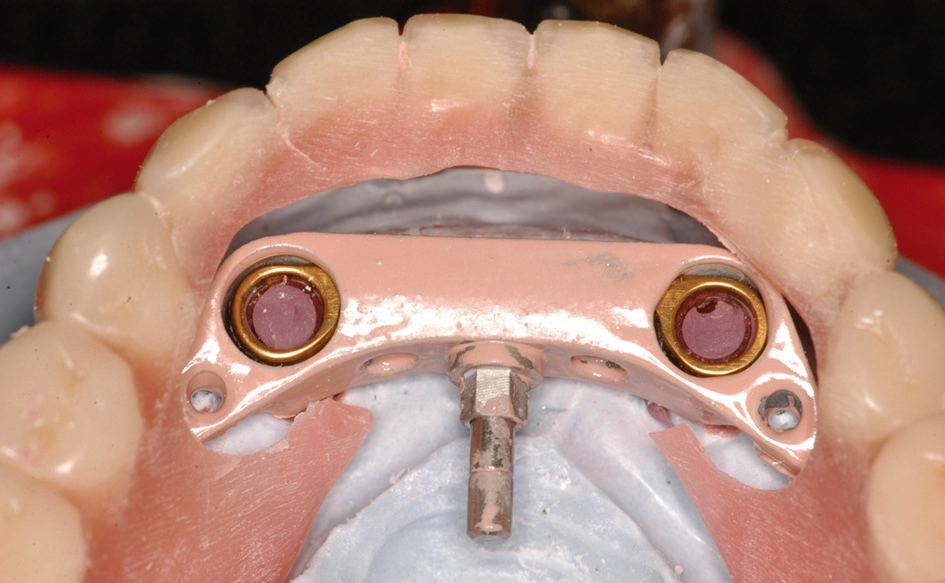

Abb. 16: Im Labor wird das Gehäuse mit dem MK-1 Riegel in die Prothese eingearbeitet.

Abb. 17: Fertige Prothese mit dem integrierten Gehäuse.